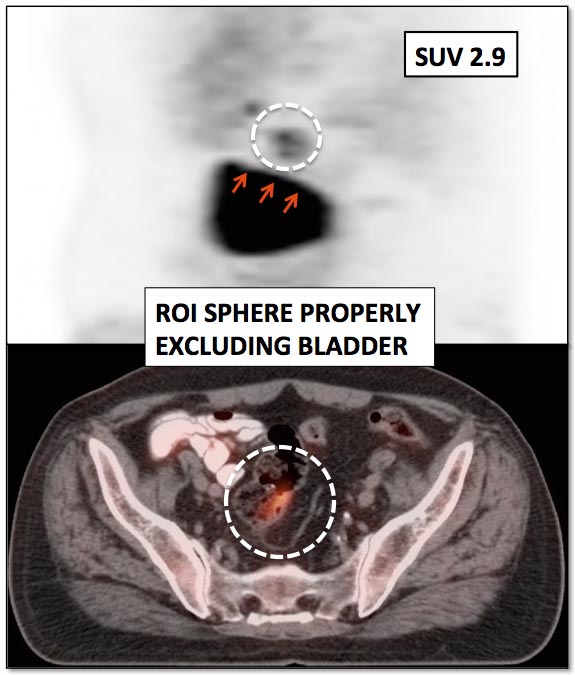

Size & Positioning of ROI:

When measuring an SUV, a region of interest (ROI) is drawn around the lesion. It is essential to assure that only the lesion is included in this ROI.

It is very easy to inadvertently include adjacent hypermetabolic structures in an ROI (frequently seen with lesions next to the heart, bladder, liver or brain), falsely increasing the measured SUV. [FIG. 8] [FIG. 9]